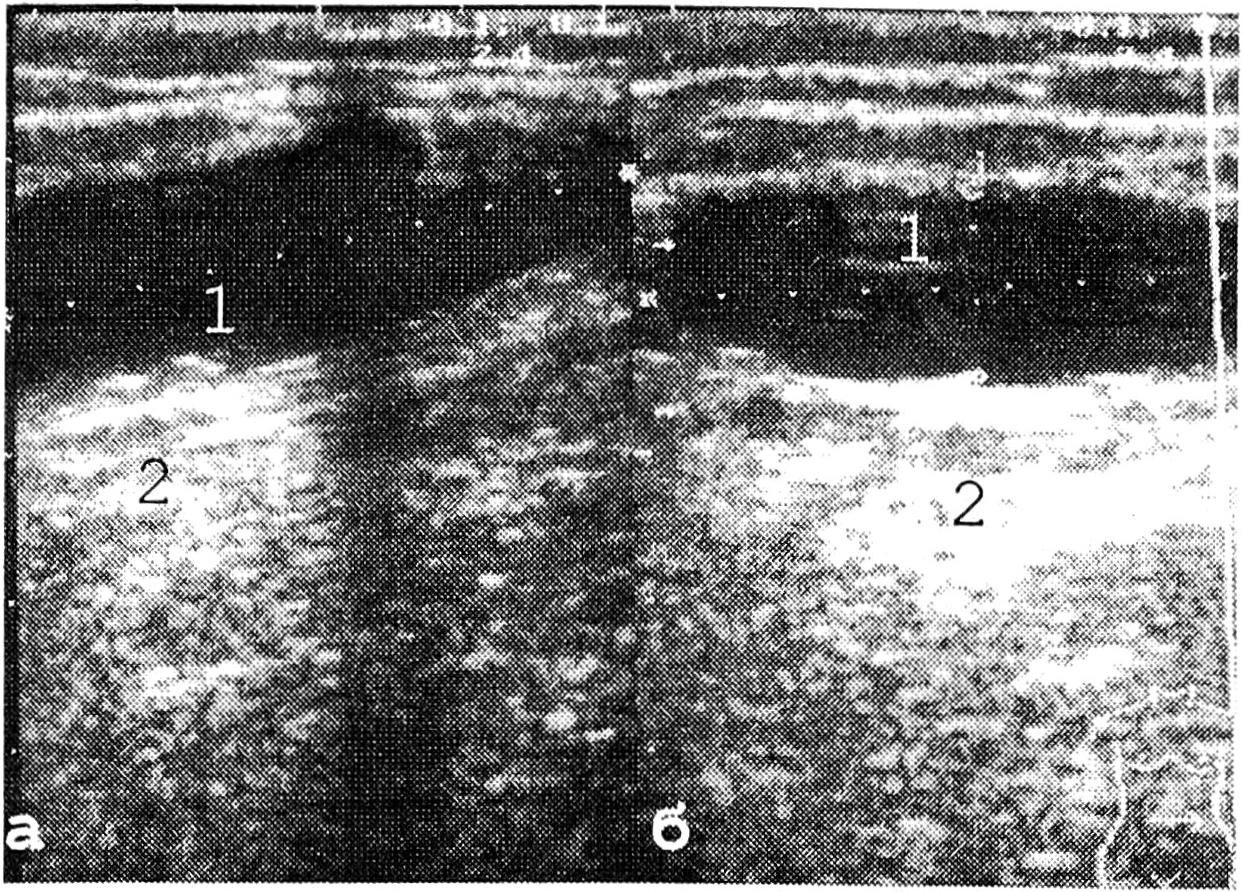

В центре абсцесса визуализировались эхонегативные зоны неправильной формы, часто с дорсальным усилением эхо-сигнала в виде широкой белой полосы, идущей вслед за задней его стенкой. Сама полость не всегда представлялась однородной, была достаточно пестрой, что зависело от степени расплавления тканей, наличия перегородок, карманов, секвестров и тканевого детрита. Обычно по периферии эхонегативного участка визуализировалось плотное кольцо шириной в несколько миллиметров, что свидетельствовало о наличии пиогенной оболочки и позволяло проводить дифференциальную диагностику абсцесса и флегмоны (рис. 11).

Рис. 11. Эхограммы нагноения послеоперационной раны: а — продольное сканирование; б — поперечное сканирование; 1 — полость гнойника; 2 — дорсальное усиление эхо-сигнала.

В виде гипоэхогенного участка с нечеткими, неровными контурами визуализировалась гематома. Когда она прилежала к фасции, контур ее был ровным. В центре наблюдаемого образования иногда находились зоны неправильной формы без отражений с неровными контурами. Дистальнее описанных зон отмечалось усиление эхо-сигнала (рис. 13).

Рис. 13. Эхограммы гематомы послеоперационной раны: а — поперечное сканирование; б — продольное сканирование: 1 — полость гематомы; 2 — дорсальное усиление эхо-сигнала.